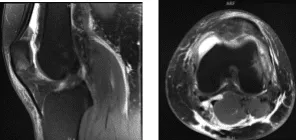

El paciente también presentó un resultado de resonancia magnética que mostró hallazgos acordes con reciente dislocación patuliana lateral transitoria con contusiones de impactación de la rótula inferomedial y del fémur distal anterolateral. Desgarro parcial en la unión rotuliana del retináculo medial. Derrame articular moderado. Quiste poplíteo parcialmente roto.

Resonancia magnética de rodilla izquierda sin contraste